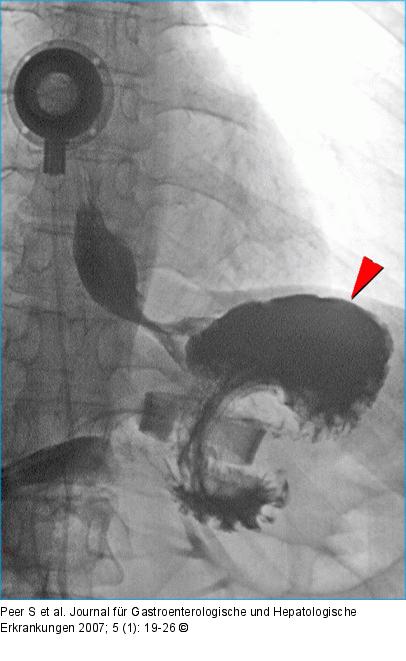

Abbildung 4: LAGB Lateral exzentrische Pouchdilatation nach LAGB: Das Magenband ist verkippt mit einem Phi-Winkel von > 90°. Kranial des Bandes findet sich ein großer, mit Kontrastmittel gefüllter Pouch (Pfeilspitze), der dem hochgerutschten Magenfundus entspricht. Die Passage durch das Magenband ist erhalten. |

Abbildung 4: LAGB